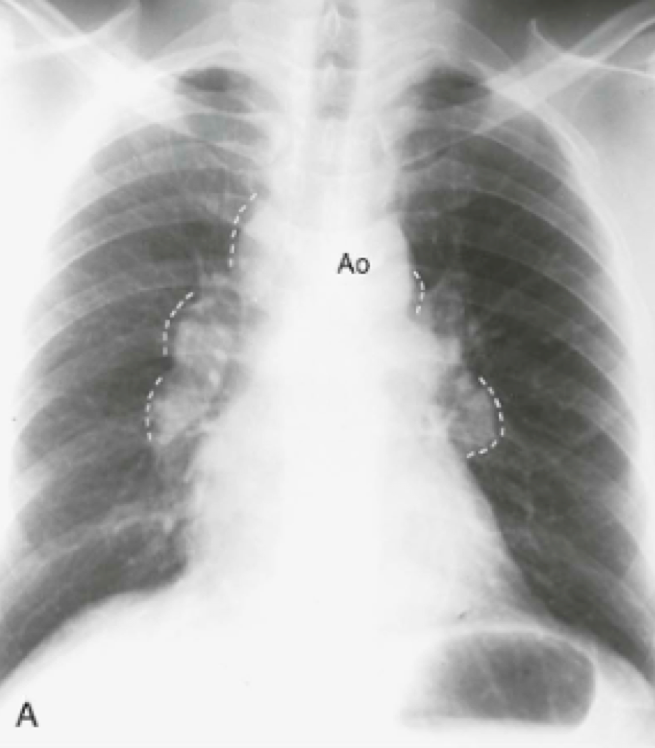

Question 14

Question

In what disease will you see this in?

Answer

• Kaposi's Sarcoma

• Silicosis

• Sarcoidosis

• Pneumocystis jiroveci